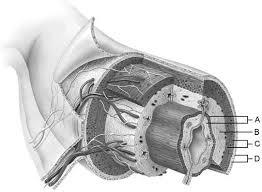

Mucosa

A

Duodenal glands found here

B

Smooth muscle layer.

C

Serosa.

D

Area of the lamina propria

A